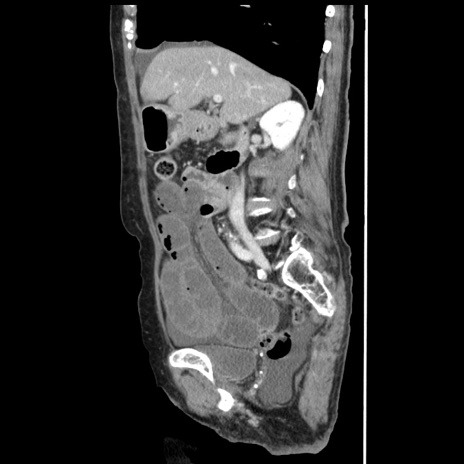

症例1(矢状断像)

【症例】80歳代女性

【主訴】腹痛

【現病歴】8時間前から腹痛あり来院。

【既往歴】糖尿病、脂質異常症、子宮体癌にて子宮全摘術

【身体所見】意識清明・会話良好だが腹痛で苦悶様、全腹部にわたって反跳痛と圧痛あり

【データ】WBC 13600、CRP 0.14、LDH 224、CK 90